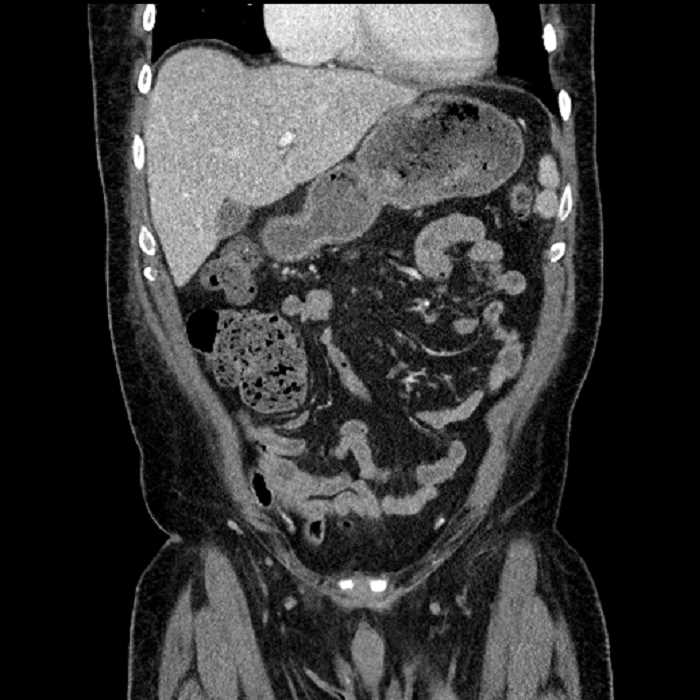

Age: 63

Sex: Male

Indication: Abdominal pain

• Mild mural thickening of a segment of the sigmoid colon with adjacent fat stranding and a 1.5 cm fluid and gas collection along the tip of an inflamed diverticulum

• Loss of the normal fat plane between this collection and adjacent loops of small bowel, which demonstrate mural thickening

• No bowel obstruction

Acute sigmoid diverticulitis complicated by a small contained perforation and a large abscess in the right hepatic lobe. Additional small subcapsular abscesses along the anterior margin of the left hepatic lobe.

Additionally, loss of the normal fat plane between the peridiverticular collection and adjacent thickened loops of small bowel raises the potential for an enterocolonic fistula.

Hepatic abscess showing the double target sign with low density internally surrounded by a thin inner enhancing rim (red arrow) and ill-defined outer low density rim (yellow arrow). Blue arrow indicates an internal septation. Red arrows: additional smaller subcapsular abscesses. Red arrow: focal contained perforation associated with diverticulitis.